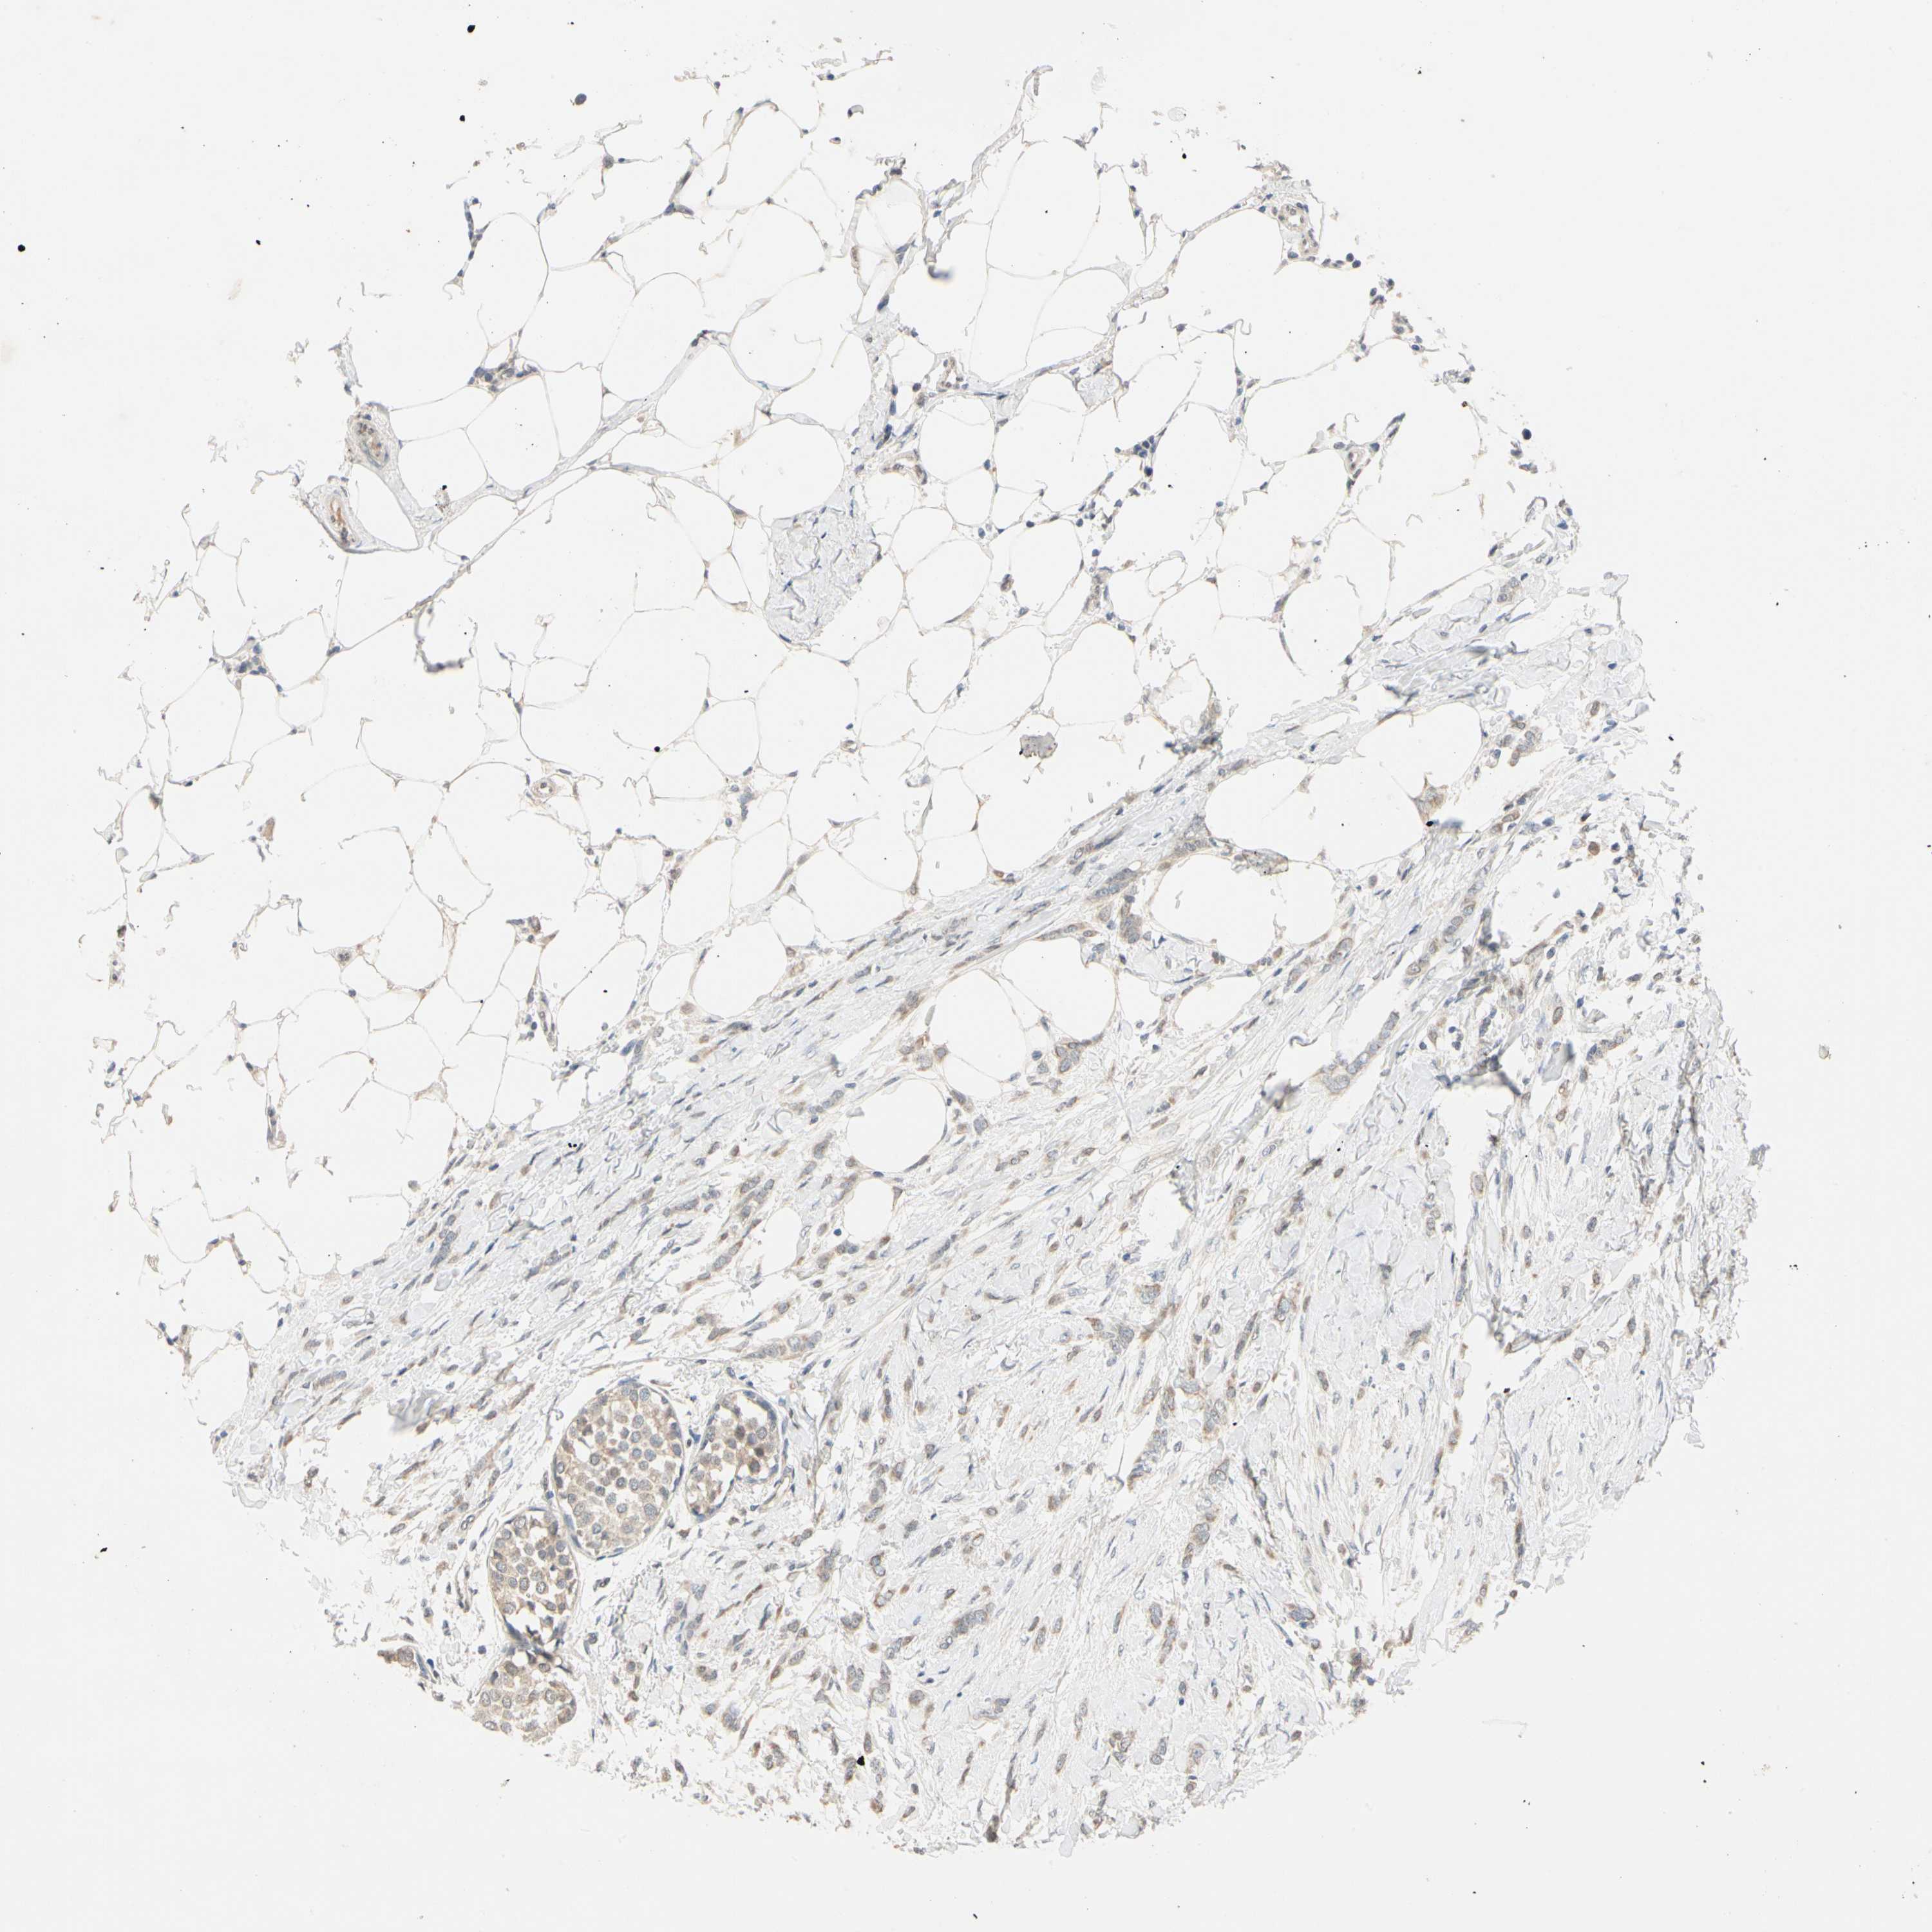

BRCA TCGA BRCA VALIDATION PROTEIN EXPRESSION